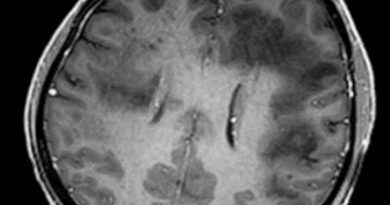

3 yaş K, santral apne, rizomeli

Tanınız nedir?